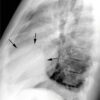

1. U trung thất trước

– Tạo góc tù với trung thất.

– Đè đẩy đường trung thất trước.

– Xóa mờ khoảng sáng sau xương ức.

– Xóa mờ góc tâm hoành.

– Xóa bờ, đè đẩy động mạch chủ lên.

– Dấu hiệu che phủ rốn phổi2. Đặc điểm u quái

– Các tổn thương lành tính thường có hình tròn, bầu dục, bờ nhẵn.

– Các u quái trưởng thành, ngấm vôi rất đậm dạng xương hoặc răng trong tổn thương. Các cấu trúc mỡ có thể biểu hiện vùng sáng hoặc có thể gặp hình ảnh mức dịch-mỡ trong tổn thương.

– Dấu hiệu ác tính: xâm lấn xung quanh: thành ngực, dịch màng phổi, dịch màng tim, di cănIV. Chẩn đoán CLVT